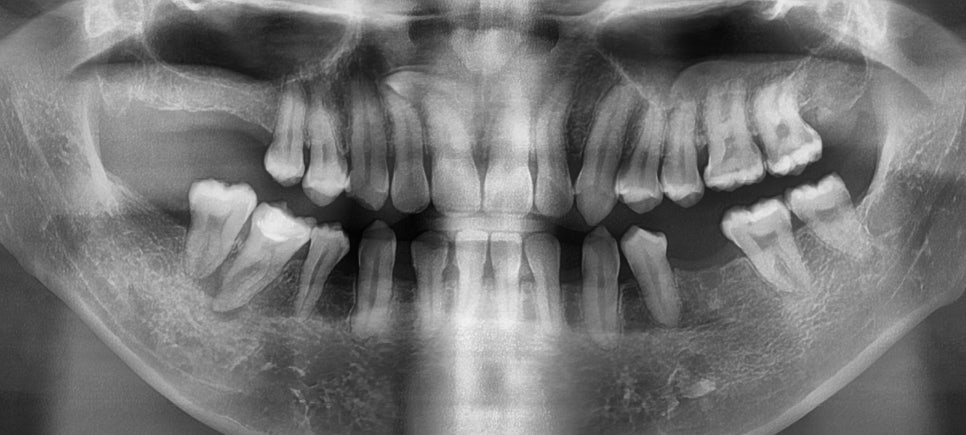

치아 결손은 치아 개수가 정상보다

부족한 상태를 말해요.

선천적으로 치아가 없거나

외상이나 질환으로 인해

치아를 잃은 경우를 포함합니다.

치아 결손이 있으면 주변 치아가

빈 공간으로 이동하게 되고,

이로 인해 전체 치열의 배열이

흐트러지게 됩니다.

특히 주걱턱과 함께 나타나면

아래턱의 돌출이 더욱 심해 보이고,

먼저 정밀한 진단과 분석을 통해

골격적 문제와 치아 배열 문제를

구분하여 평가합니다.

23.09.01

3차원 영상 분석과 모델 분석을 통해

치료 계획을 수립하게 되어요.